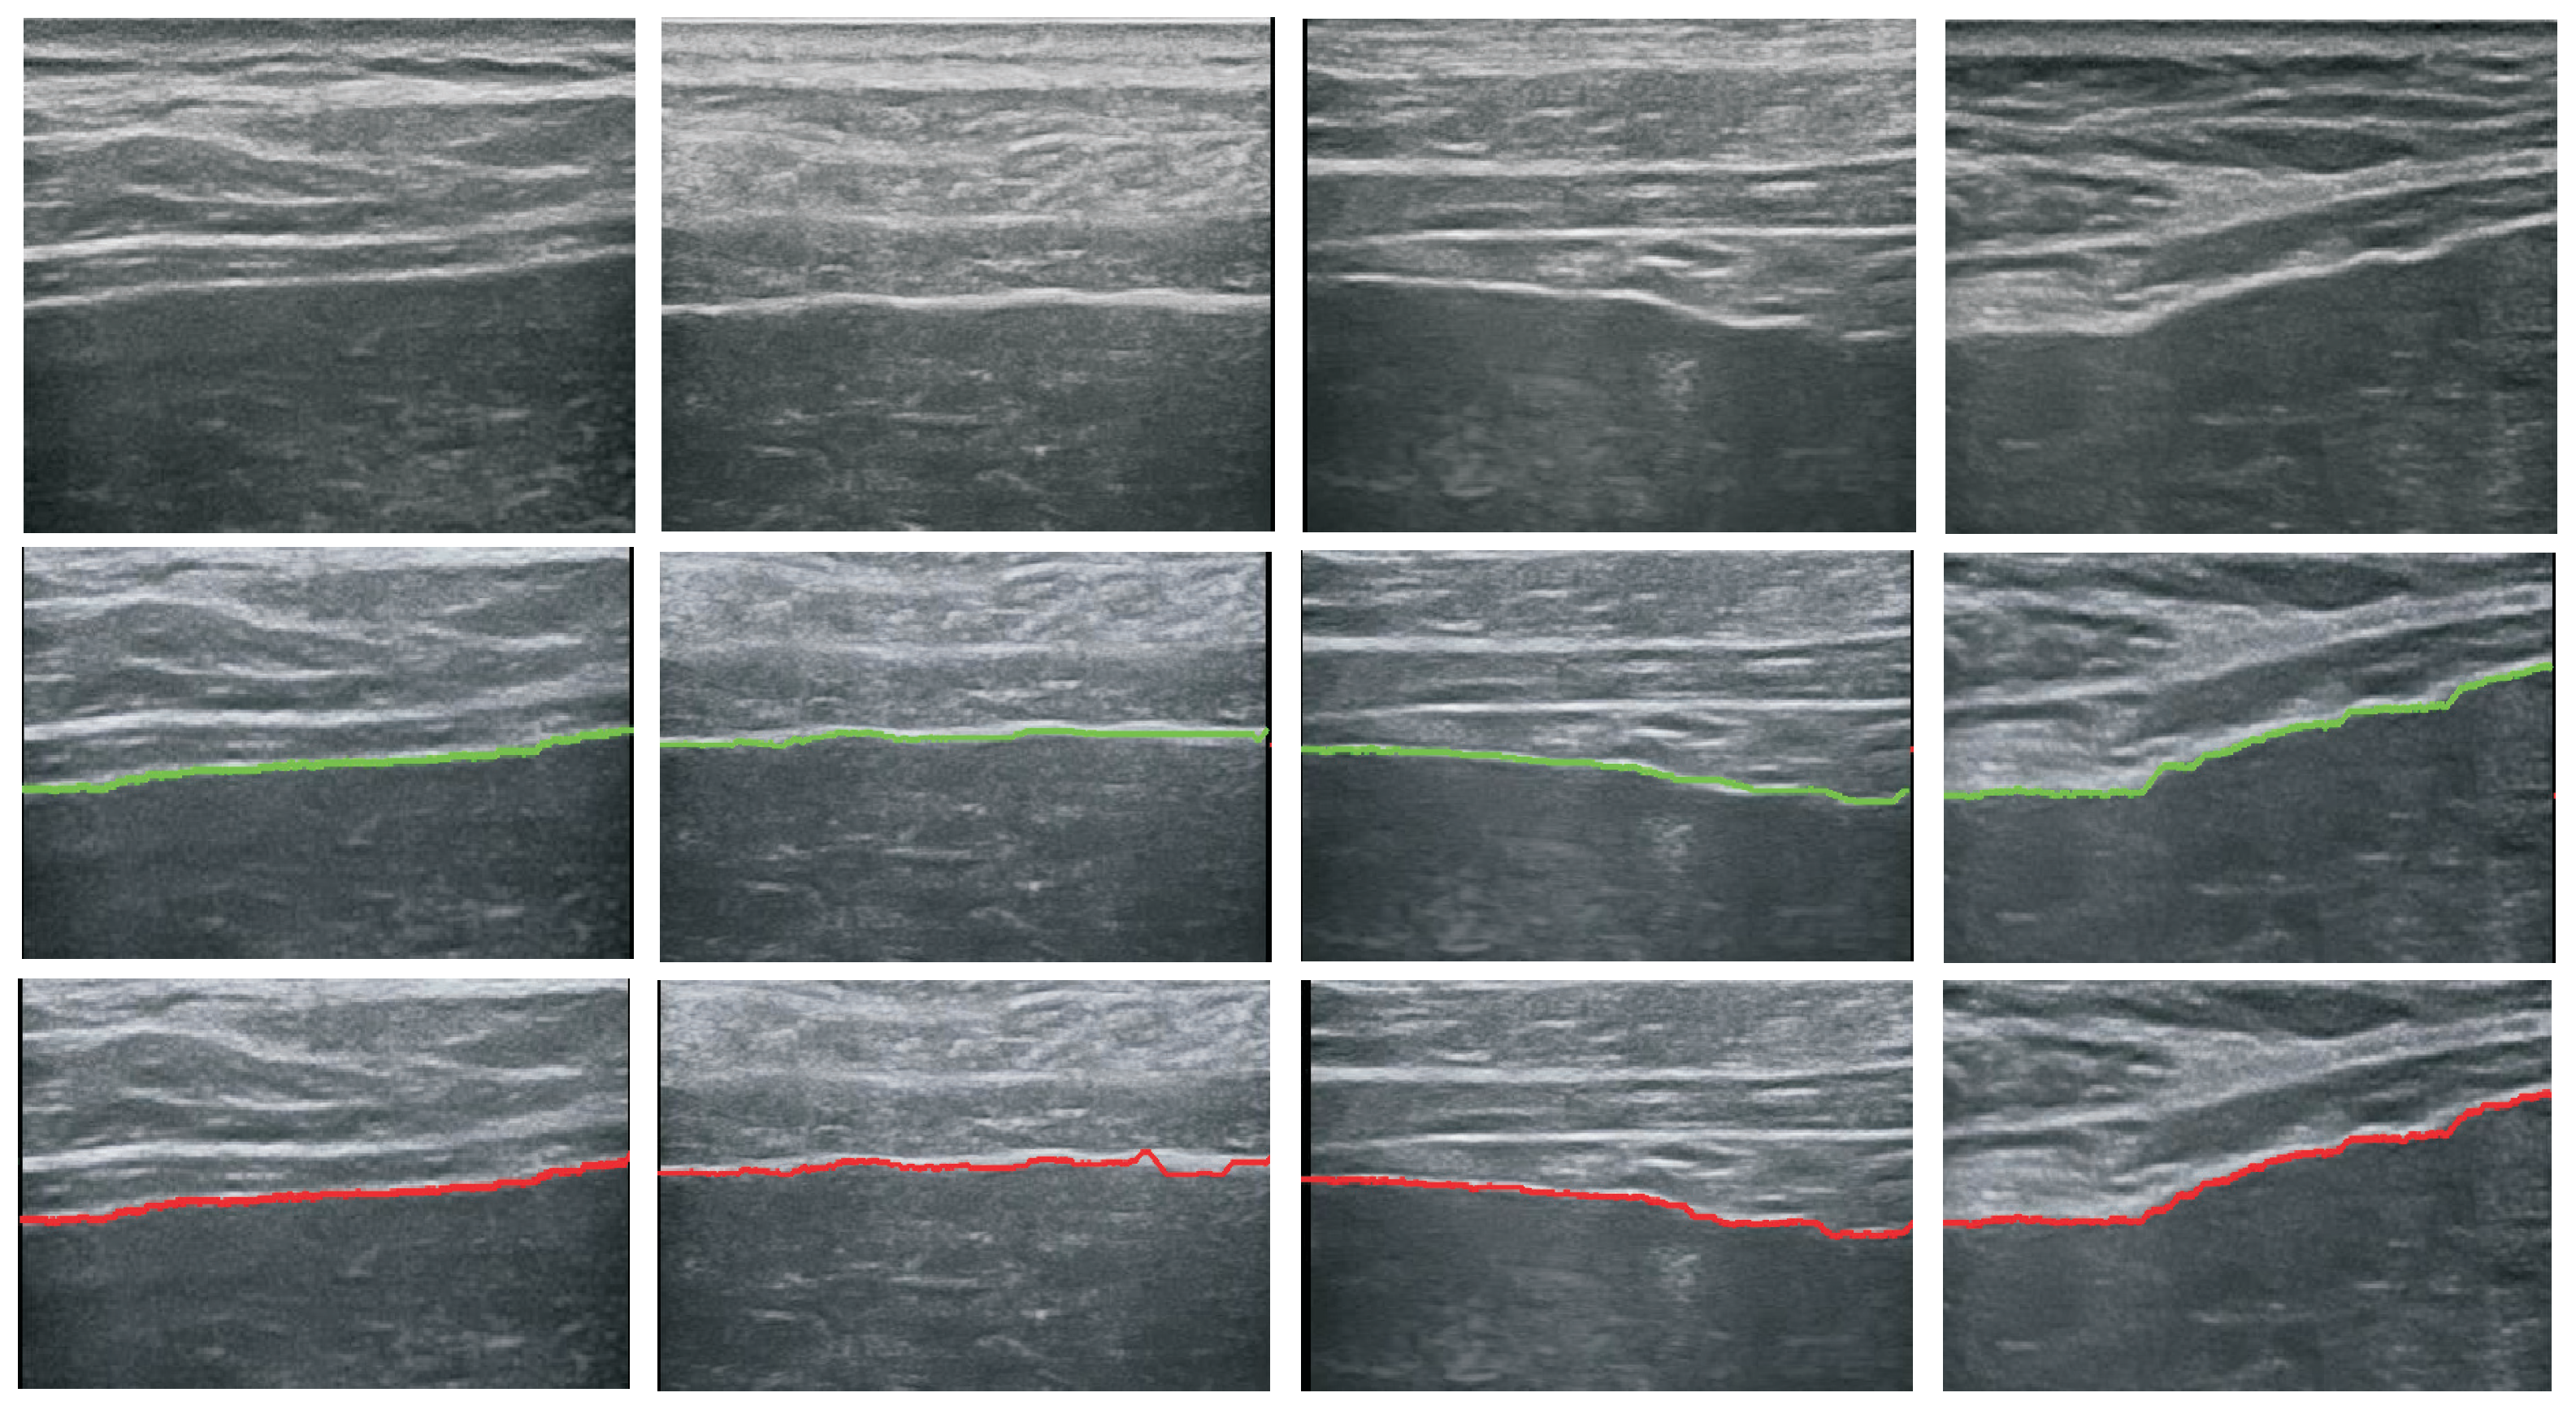

5.1. Performance of the Detector